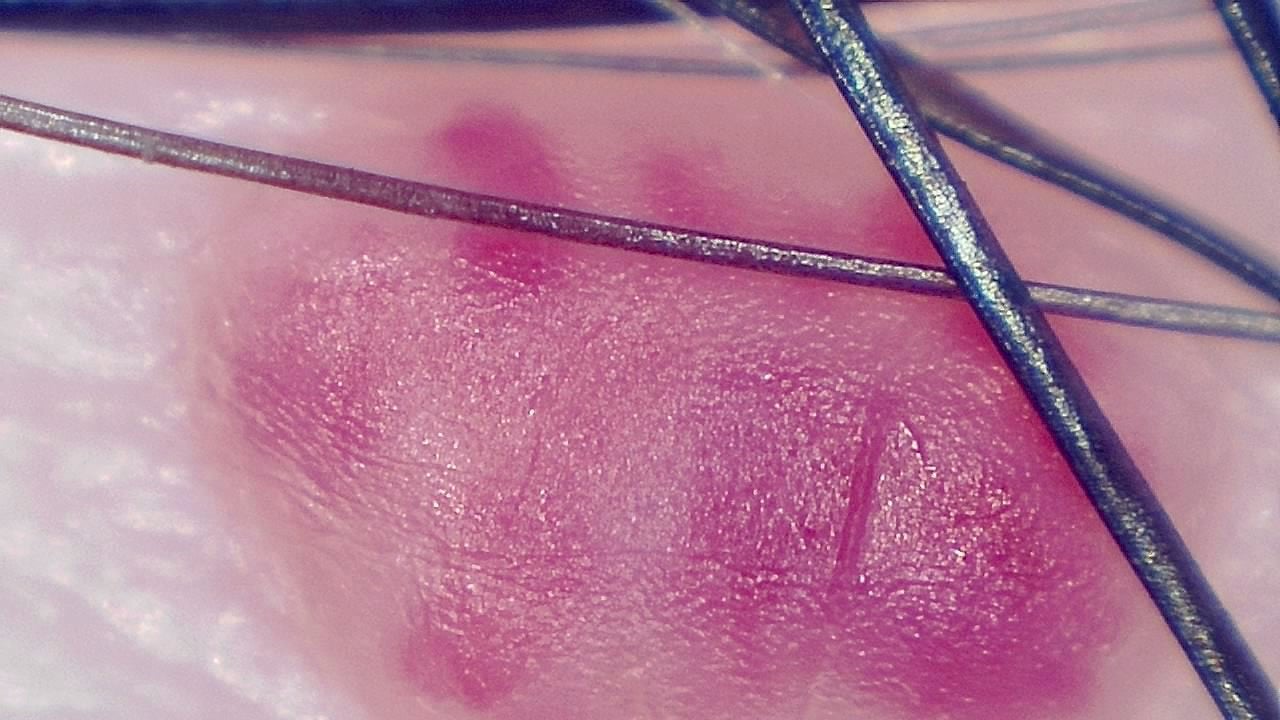

With variable magnification, it is possible to examine everything from superficial structures to deeper epidermal layers, identifying pigmentation patterns, abnormal vascularization, and textural changes that may go unnoticed to the naked eye.

- Visualization of dermal structures with up to 250× magnification

Atypical nevus follow-up

A dermatologist uses Smart G-Scope to document a suspicious nevus during quarterly check-ups. Comparative images help detect subtle changes in borders and pigmentation, supporting an earlier decision to refer for biopsy before the lesion progresses.